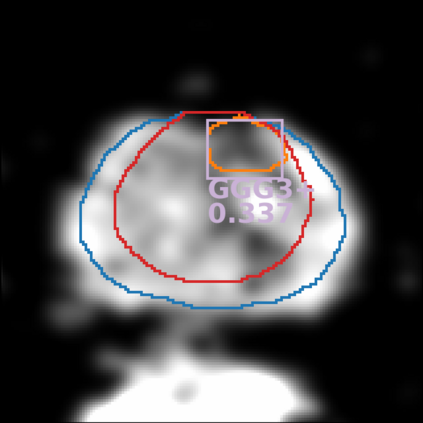

The emergence of multi-parametric magnetic resonance imaging (mpMRI) has had a profound impact on the diagnosis of prostate cancers (PCa), which is the most prevalent malignancy in males in the western world, enabling a better selection of patients for confirmation biopsy. However, analyzing these images is complex even for experts, hence opening an opportunity for computer-aided diagnosis systems to seize. This paper proposes a fully automatic system based on Deep Learning that takes a prostate mpMRI from a PCa-suspect patient and, by leveraging the Retina U-Net detection framework, locates PCa lesions, segments them, and predicts their most likely Gleason grade group (GGG). It uses 490 mpMRIs for training/validation, and 75 patients for testing from two different datasets: ProstateX and IVO (Valencia Oncology Institute Foundation). In the test set, it achieves an excellent lesion-level AUC/sensitivity/specificity for the GGG$\geq$2 significance criterion of 0.96/1.00/0.79 for the ProstateX dataset, and 0.95/1.00/0.80 for the IVO dataset. Evaluated at a patient level, the results are 0.87/1.00/0.375 in ProstateX, and 0.91/1.00/0.762 in IVO. Furthermore, on the online ProstateX grand challenge, the model obtained an AUC of 0.85 (0.87 when trained only on the ProstateX data, tying up with the original winner of the challenge). For expert comparison, IVO radiologist's PI-RADS 4 sensitivity/specificity were 0.88/0.56 at a lesion level, and 0.85/0.58 at a patient level. Additional subsystems for automatic prostate zonal segmentation and mpMRI non-rigid sequence registration were also employed to produce the final fully automated system. The code for the ProstateX-trained system has been made openly available at https://github.com/OscarPellicer/prostate_lesion_detection. We hope that this will represent a landmark for future research to use, compare and improve upon.